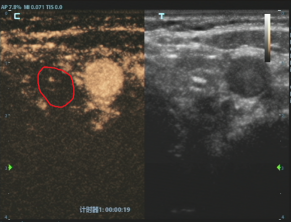

消融后病灶

这个方案瞬间让刘女士放下了所有的担忧。随后,白国栋主任团队便为她实施了超声引导下甲状腺结节射频消融术,整个过程仅十几分钟。治疗结束时,刘女士几乎不敢相信地说,“就这么好了?我根本没有任何不舒服的感觉。”

白国栋主任介绍,甲状腺微小乳头状癌通常发展缓慢,预后极好,患者不必过度恐慌。射频消融术作为一种成熟的超微创治疗手段,正是为这类符合条件的早期患者提供了更优选择,能完美满足患者“保功能、无疤痕、快恢复”的核心需求,科室已将其作为常规治疗方案,技术非常成熟。消融后的坏死组织通常在1-2年内会被身体逐渐吸收,甚至完全消失。即便未来出现新发或复发情况,仍有再次消融或手术等补救措施作为保障。